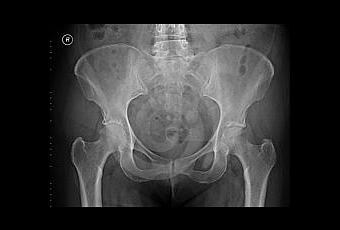

En medio de la escasez de radiólogos en el Reino Unido y una exigencia cada vez mayor para los investigadores que trabajan con grandes bases de datos de imágenes de radiografías, el software que está siendo financiado por Engineering and Physical Sciences Research Council, está siendo diseñado para que marque automáticamente a las formas de los huesos en las imágenes de rayos X, en lugar de depender de los investigadores individuales.

El sistema ya puede identificar las caderas, pero los investigadores del Institute of Population Health de la Universidad lo han adaptarlo para trazar rodillas y manos y ser capaz de aprender a identificar otros huesos y estructuras dentro del cuerpo.

La financiación de 300 000 £ tiene una duración de tres años y se basa en trabajos anteriores que desarrollaron el software, llamado Bonefinder, para identificar los problemas y encontrar las líneas generales de las caderas. Este software libre ha sido adoptado por un número de grupos de investigación, entre ellos algunos con sede en Oxford y California.